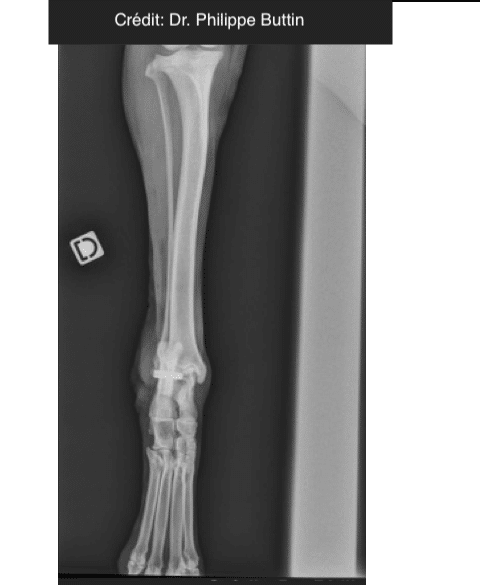

Achilles Tendon Repair

Radiologické snímky